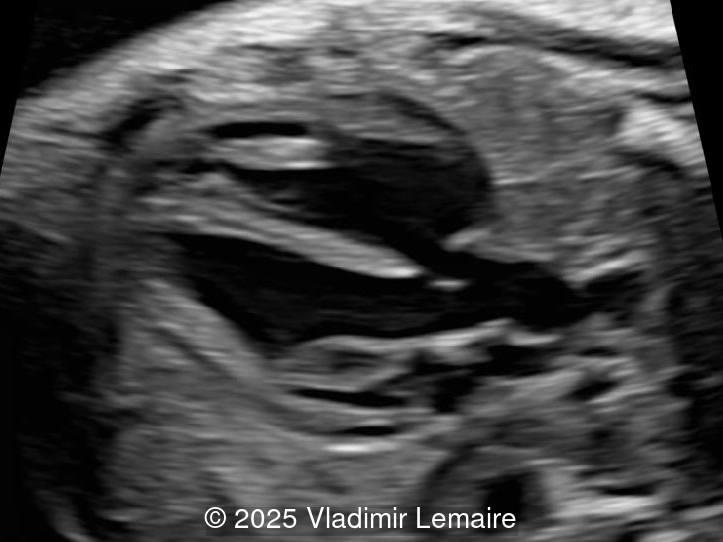

- Images 3 and 4: The five-chamber view shows the ventricular septal defect and the dilated overriding aorta.

In Tetralogy of Fallot, the four-chamber view typically appears normal unless a large ventricular septal defect is visible in this plane. TOF is usually detected in the left ventricular outflow tract view, which demonstrates a perimembranous, subaortic ventricular septal defect with an overriding aorta. The overriding aorta is due to the discontinuity between the interventricular septum and medial wall of the aorta (malalignment VSD). This results in a partial connection of the aorta to the right ventricle, with an aorta that is slightly shifted to the right, referred to as aortic dextroposition. The aortic root appears dilated, especially in the third trimester, because it receives blood from both the right and left ventricles. The overriding aorta has a parallel course to the interventricular septum in contrast to the ascending aorta in a normal heart.

Color Doppler confirms the presence of an overriding aorta with blood draining from both ventricles, through the ventricular septal defect into the aortic root. Due to high perfusion, inflow into the aorta appears aliased. At the level of the three-vessel-trachea view, color Doppler can also demonstrate a small pulmonary artery. Flow is antegrade across the ductus arteriosus in mild Tetralogy of Fallot and can be reversed in severe cases. Color Doppler can help differentiate various subgroups of TOF as postnatal ductal dependency of the pulmonary circulation can be associated with cyanosis of the newborn.